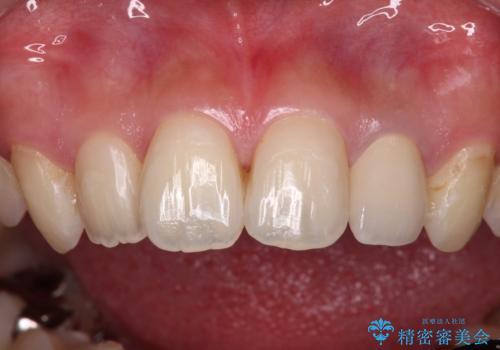

- 根管治療後に10年以上経過し、変色した前歯を気にして来院された患者様です。

根管治療はやり直さずに、ファイバーポストを使用した土台を植立してオールセラミッククラウンにて補綴することとしました。

神経を取り除いた歯は時間とともに変色してきます。

クリーニングやホワイトニングでは改善できないため、オールセラミッククラウンなどによる補綴治療が必要となります。